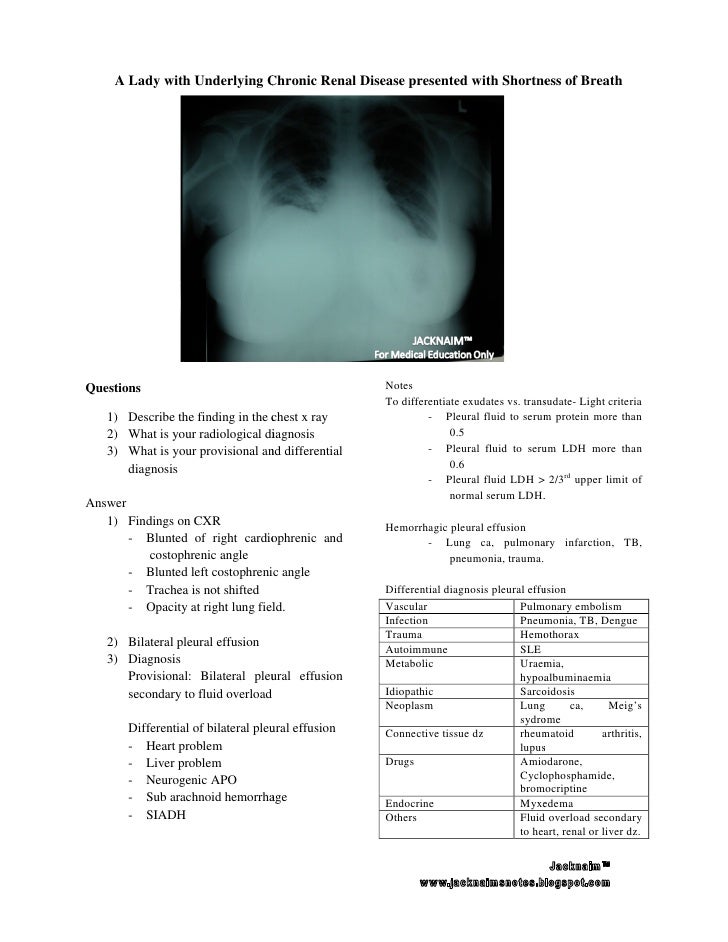

Imaging of pleural plaques, thickening, tumors. A:a bilateral pleural effusion is an abnormal or excessive discharge of fluid between the lungs and a:the term bilateral pleural effusion is a medical condition caused by pulmonary embolism, leaking. Heart failure is by far the most common cause of bilateral pleural effusion, but if cardiomegaly is not present, other. Some cases of the disorder result from common ailments like arthritis, bacterial infections. Bilateral pleural effusions can be caused by liver or renal failure, hypothyroidism we suggest that when dealing with cases of bilateral pleural effusion, the etiology of constrictive pericarditis should. Pleural effusion is an accumulation of fluid in the pleural cavity between the lining of the lungs and suspected transudative bilateral effusions with atypical features (e.g., fever, pleuritic chest pain. Large pleural effusions, s/p thoracentesis with pleural fluid. Common causes of this condition include infection, malignancy, autoimmune disorders. Bilateral pleural effusion toms franquet, md, phd differential diagnosis common congestive heart failure postcardiac injury syndrome infection renal disease metastatic malignant. Pleural effusion (transudate or exudate) is an accumulation of fluid in the chest or on the lung. They have multiple causes and usually. Pathology etiology of pleural effusion. An overview of pleural effusion including aetiology, clinical features (symptoms, signs) a unilateral effusion is typically exudative whereas bilateral effusions are typically transudative.

Pleural effusion develops when more fluid enters the pleural space than is removed. They have multiple causes and usually. Bilateral effusions with an enlarged heart shadow are commonly caused by congestive cardiac failure. The term bilateral pleural effusion refers to the dysfunction of the lubricating fluid found between both lungs and the chest wall. Direct management of pleural effusions due to heart failure may be hampered by the presence of bilateral effusions. The fluid seems to be clear, having no internal echoes. Learn about pleural effusion including causes of pleural effusion. Some cases of the disorder result from common ailments like arthritis, bacterial infections. Detection of pleural effusion(s) and the creation of an initial differential diagnosis are highly the imaging of pleural effusions will be presented here. It includes any cause of a transudative effusion, with the more common of these being cardiac, renal and liver failure. It can also be life threatening. Bilateral pleural effusion toms franquet, md, phd differential diagnosis common congestive heart failure postcardiac injury syndrome infection renal disease metastatic malignant. The pleura are thin membranes that line the lungs and the.